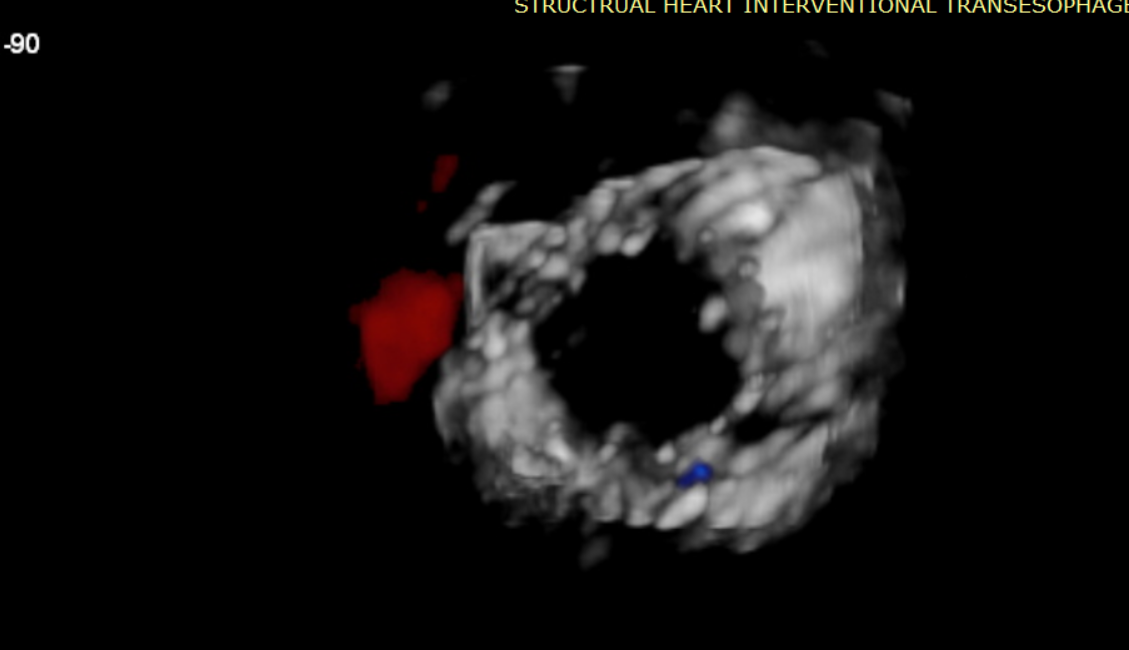

術前超聲提示大量三尖瓣反流

術中輸送器在超聲引導下調整位置

術后超聲提示無瓣周漏

術后超聲提示僅殘余輕微瓣周漏